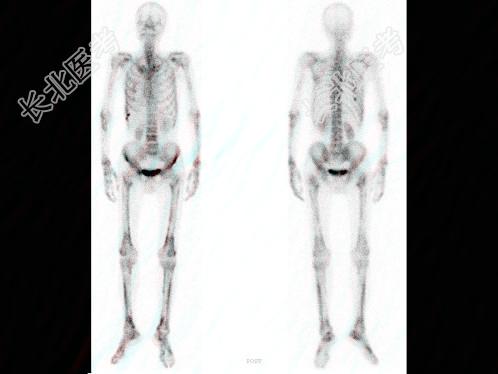

多项选择题男,68岁, 肺癌术后半年,诉双下肢疼痛3个月, 行全身骨显像如图,可能的诊断是 ( )

A、广泛骨转移瘤

B、双侧下肢骨骨转移瘤

C、双下肢肥大性骨关节病

D、热髌征存在